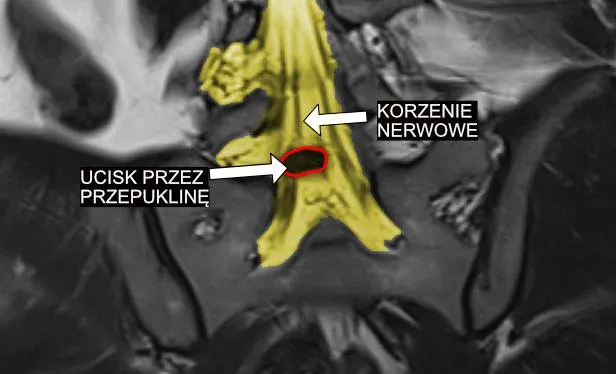

Z mojego doświadczenia wynika, że najczęstszą przyczyną zaburzeń korzeni rdzeniowych jest dyskopatia, czyli przepuklina krążka międzykręgowego. Kiedy jądro miażdżyste krążka wypchnie się poza swoje naturalne granice, może uciskać na nerw, wywołując silny ból i inne objawy neurologiczne. Ale to nie jedyny winowajca. Oto inne, równie istotne przyczyny:

Rezonans magnetyczny (MRI): złoty standard w obrazowaniu przyczyn ucisku

Kiedy podejrzewam ucisk na korzenie rdzeniowe, rezonans magnetyczny (MRI) jest dla mnie badaniem z wyboru. To złoty standard w obrazowaniu tkanek miękkich, który pozwala mi precyzyjnie ocenić stan krążków międzykręgowych, więzadeł, rdzenia kręgowego i samych korzeni nerwowych. Dzięki MRI mogę zobaczyć przepukliny, zmiany zwyrodnieniowe, stenozy, a nawet guzy, które mogą być przyczyną dolegliwości. Badanie to dostarcza niezwykle szczegółowych informacji, które są kluczowe do zaplanowania leczenia. Uzupełniająco, w specyficznych przypadkach, mogę zlecić tomografię komputerową (TK) lub zdjęcia rentgenowskie (RTG), zwłaszcza gdy chcę ocenić strukturę kostną kręgosłupa.